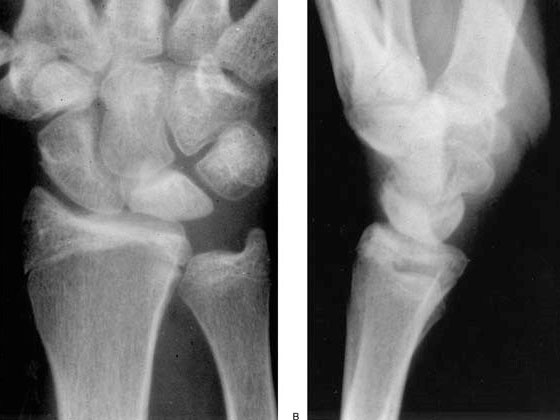

Radiografía simple.

La radiografía puede mostrar cambios en la densidad del semilunar, esclerosis, pérdida de altura, colapso o signos degenerativos en fases más avanzadas. También puede ayudar a identificar variantes anatómicas asociadas, como el cúbito corto.

TAC

La tomografía computarizada puede ser útil para valorar con más precisión la estructura ósea, el grado de colapso, la fragmentación del semilunar y el estado del carpo, lo que ayuda a afinar el estadiaje y la planificación quirúrgica cuando es necesaria.

La clasificación más utilizada es la clasificación de Lichtman, que divide la enfermedad en distintos estadios clínico-radiológicos y orienta el tratamiento.

Estadio III

El semilunar empieza a colapsarse y se distinguen dos subtipos.

Estadio IIIA

Existe colapso del semilunar, pero se mantiene mejor la arquitectura general del carpo.

Estadio IIIB

Además del colapso, aparece alteración de la alineación carpiana, como rotación fija del escafoides o colapso del carpo.

Estadio IV

Existe una afectación avanzada, con destrucción del semilunar y cambios degenerativos artrósicos en la muñeca.